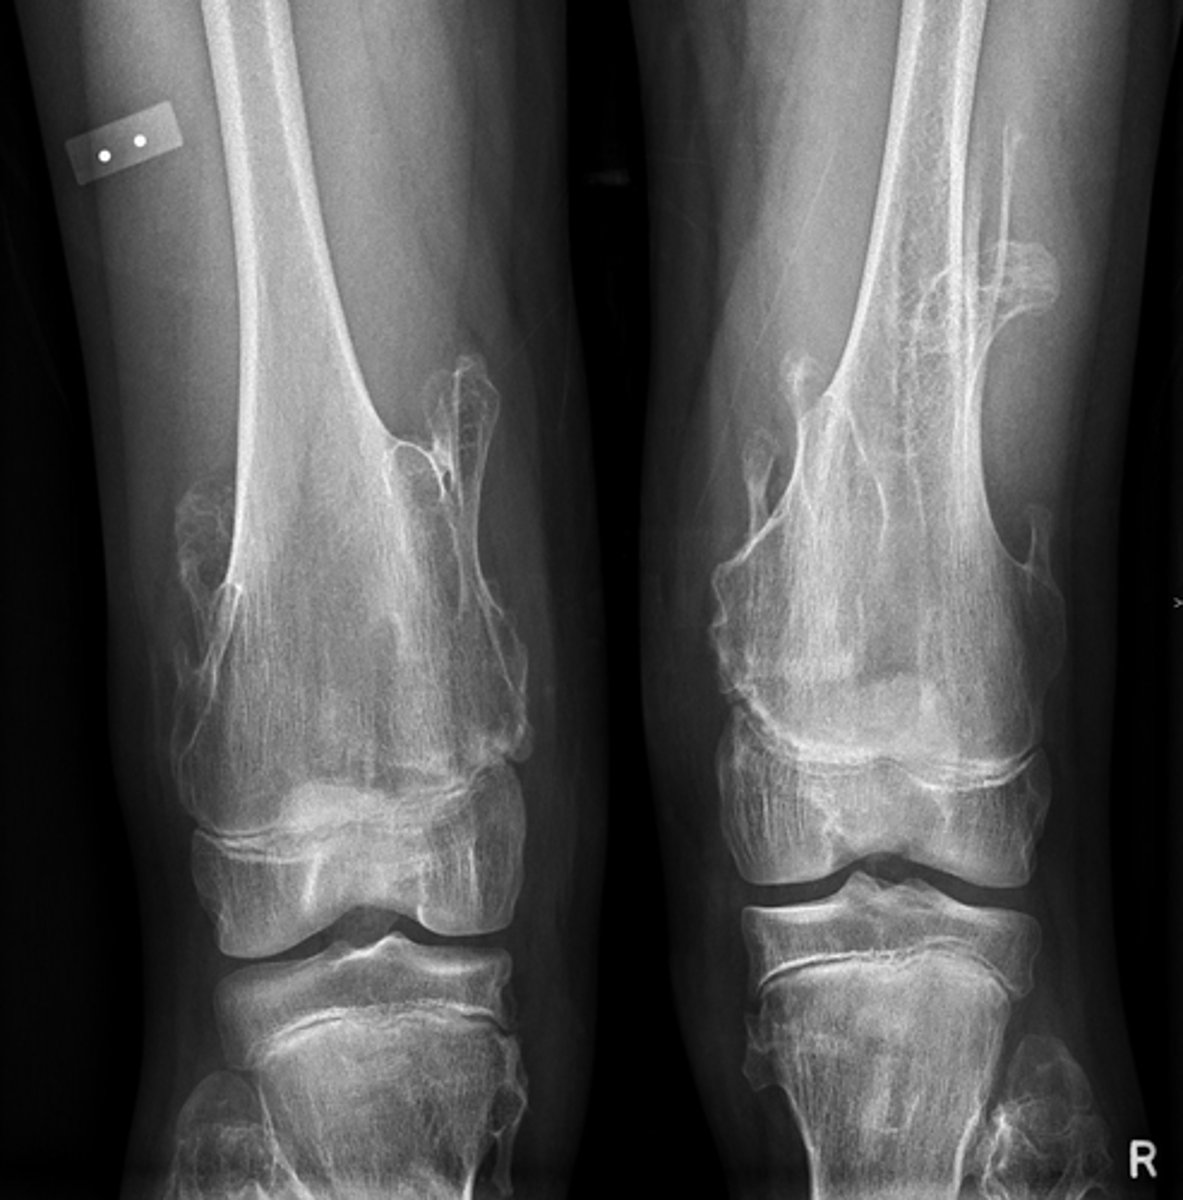

Lateral proximal tibia

Bone

<p>Bone</p>

- Longitudinal: epiphysis/metaphysis (up to joint surface)

- Eccentricity: eccentric

- Transverse: medullary

Location

- Lytic

- Geographic

- Short zone of transition

Behavior

<p>Behavior</p>

Giant cell tumor

Most likely diagnosis?

<p>Most likely diagnosis?</p>

Refer to orthopedist or oncologist

Next step?

<p>Next step?</p>

Could be aggressive (20%)

Concerns/complications?

<p>Concerns/complications?</p>